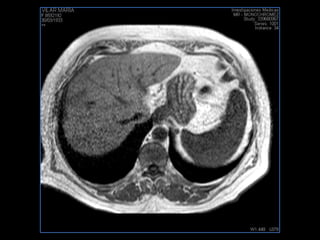

PROTOCOLO hígado graso AXIAL in phase y out phase AX T1 y AX fat sat +SAG T2  CON   GADOLINIO :  COR T1+AX T1(DIN) SAT: NO  FASE: RL THK: 4MM  COIL:  GAP: (FACTOR 1.4)  FOV: 40 CM NEX:2 SINCRONIZACION RESPIRATORIA EN 3 O 4 CICLOS ALE